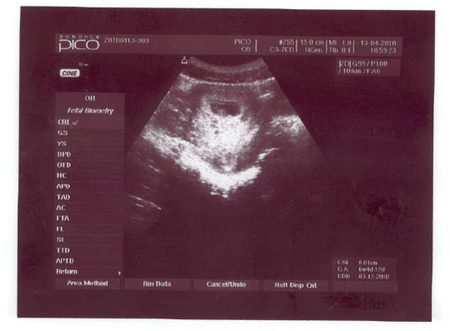

Вчера на работе, отсканировала фото узи малого.Т ам есть 1-ое узи, сделанное в 3-4 недели, чтоб быть уверенной, что не внематочная, потом в 6 неделек, там у меня началась отслойка и появилась деформация плодного яйца, слава богу, что малыша удалось сохранить, назначили ударные порции дюфастона, витаминок, папаверина при болях и постельный режим. А 3-е и 4-ое узи, это 12-ть и 24 недельки, там у нас все отлично))))Хотя в 24 недельки я попросила еще сделать доплер и не зря, обнаружилось нарушение кровотока 1-ой степени, типа пока малышу все хватает, но все равно надо пролечится, поэтому полежала в больничке, прокапали капельницы с актовегинчиком и все пришло в норму. следующее узи будем делать в 32 недельки, а пока выставлю отсканированные фоточки)))